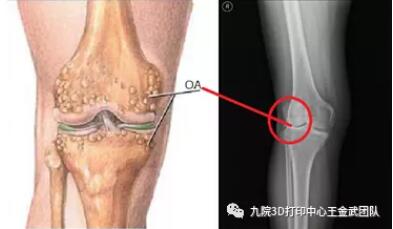

随着老龄化社会的步入,老年人口数的不断上升,骨关节炎(OA)也成为威胁中老年人群健康,致残中老年人群的主要因素之一。全球约有1.9亿OA患者,且人数不断增加,发病率随年龄递增,小于40岁为5%,60岁~75岁高于50%,大于75岁高达80%。膝关节骨性关节炎是OA的最常见类型,是一种慢性、无菌性、进行性侵犯关节的炎症,最终致关节疼痛,畸形和功能障碍,影响病人的活动能力和生活质量。资料表明60岁以上人群,几乎100% 有膝关节退变的组织学表现,60%~80%可见OA的X线征象,其中20%有疼痛和活动受限;国内的发病率高达8.3%。

膝骨关节炎的诊断

下肢力线的测量一般采用负重位下肢力线全长X线片进行测量。

除此之外,胫股角也常被用作膝骨关节炎的诊断。胫股角是股骨长轴和胫骨长轴相交于膝关节中心而形成的向外侧的夹角,平均为174°图片图片。